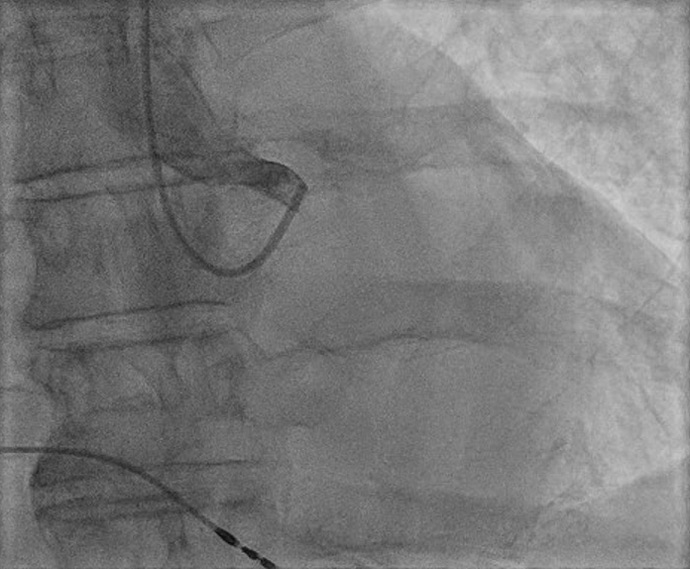

A 66-year-old male patient was brought in for urgent coronary angiography due to cardiogenic shock. ECG showed a paced rhythm with intermittent ST-elevation in aVR and global ST depression. He had a history of permanent atrial fibrillation and a permanent pacemaker.

An image is worth a 1,000 words: participate in the quiz below to tell us what you see in this image!